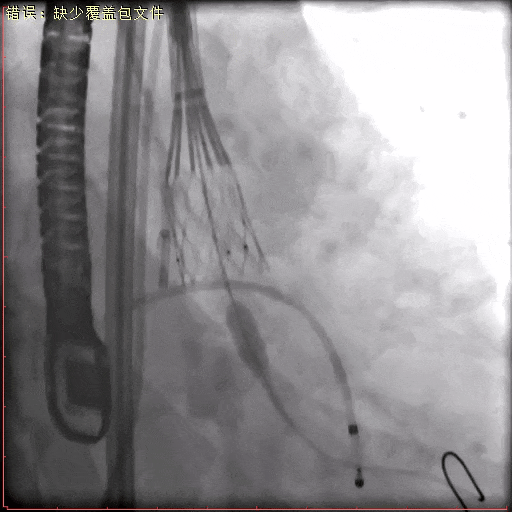

术中造影

20 mm球囊预扩张

瓣膜定位

瓣膜稳定释放至全展开位

脱钩后最终造影